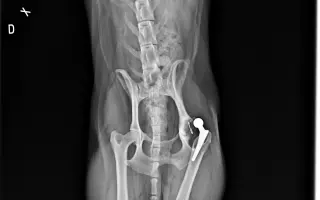

Akutní operace kyčle pro Charlieho: pomozte mu opět běhat bez bolesti